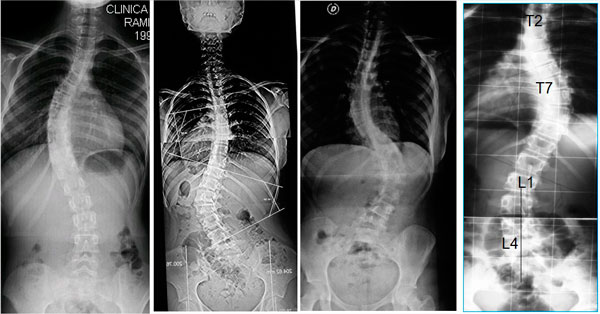

¿Cómo se ve la escoliosis en la radiografía?

- La escoliosis viene definida por la región de la columna vertebral donde surge la curva (columna torácica alta, columna torácica o columna lumbar).

- La escoliosis puede localizarse en uno o más segmentos: curva simple, curvas dobles o triples.

- La dirección de la curva puede ser derecha o izquierda.

La escoliosis puede localizarse en uno o más segmentos: curva simple, curvas dobles o triples. La dirección de la curva puede ser derecha o izquierda.

Ejemplos de diferentes curvas y diversas localizaciones.